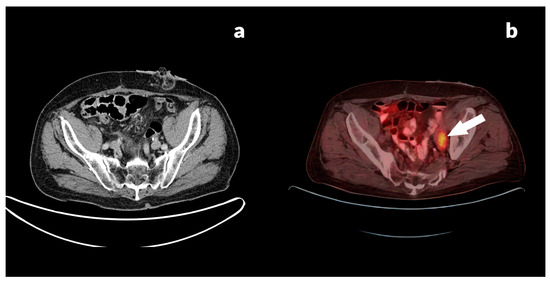

3.2.3. Case Reports